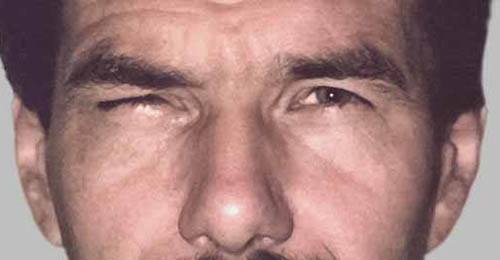

Protruding eyes (exophthalmus) in Graves’ disease

Chronic immune system-mediated inflammation can lead to an increased amount of connective tissue forming behind the eye, which pushes the eyeball forward – and severely limits its mobility. These changes also cause the eye muscles to swell.Please note that orbital decompression in protruding eyes in Graves’ disease can only be treated once the orbit shows no more signs of active disease and is “calm” for 12 months.”